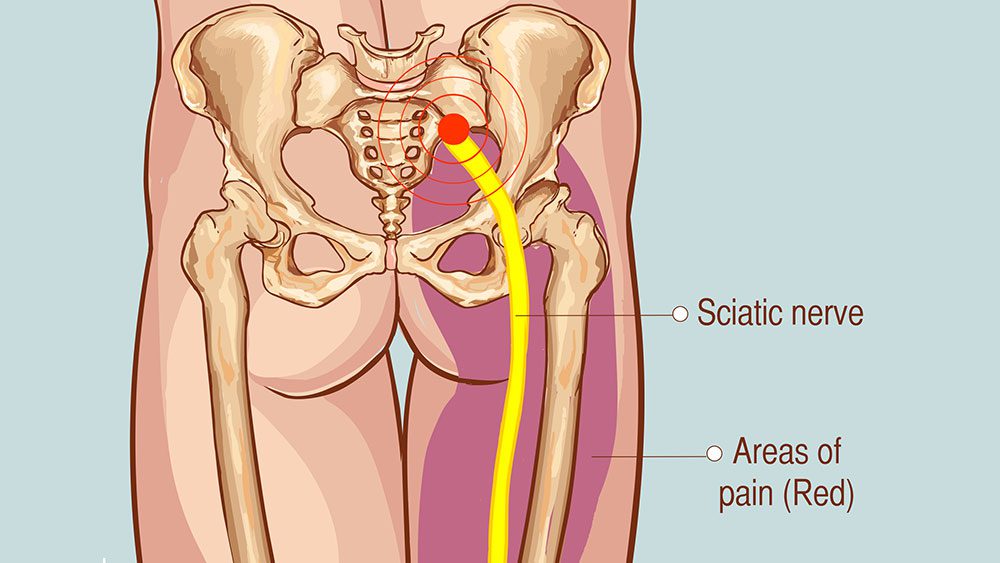

Download Sciatic nerve pain pictures